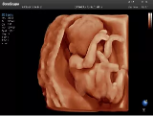

4容積探頭

積探頭是在二維圖像的基礎(chǔ)上,將連續(xù)采集的空間分布位置,經(jīng)過計算機(jī)重建算法,從而獲得完整的空間形態(tài)。

適用于:胎兒面部、脊柱和肢體等。

優(yōu)勢特點:快速獲取、掃查連續(xù)均勻、解剖結(jié)構(gòu)顯示為容積數(shù)據(jù)、準(zhǔn)確進(jìn)行容積測量。